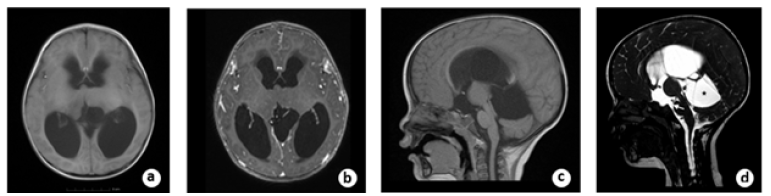

A 22-month-old boy with a history of headache and vomiting who was presented with signs and symptoms of high intracranial pressure for two weeks was referred to our hospital. The Magnetic Resonance Imaging (MRI) revealed an isointense lesion on a T1-weighted image without enhancement following contrast agent administration in the left thalamus. There was a big cyst located above the cerebellum and inferior to the tentorial region. Because of the obstruction of the Moron holes and the distortion of the aqueduct, the ventricles were enlarged, and the periventricular edema was obvious bilaterally. The sagittal view of Three-Dimensional Fast Imaging Steady Acquisition (3D FIESTA) revealed the sank of the third ventricular floor because of the obstructive hydrocephalus and a big cyst located inferior to the tentorial (Figure 1). Virtual Endoscopy (VE) based on 3D FIESTA data made from 3D Slicer software revealed the dilated Moron hole bilaterally, the narrow space between the lesion and the fornix and the opening of the cyst superior to the cerebellum (Figure 2).

Figure 1a: pre-operative axial view of T1-wighted MRI showed the tumor located in the left thalamic region and the ventricles were enlarged bilaterally. B. The tumor was not enhanced after contrast material administration. C. The aqueduct was distorted by the compression of the cyst located superior to the cerebellum. D. pre-operative sagittal view of 3D FIESTA showed the sink of the third ventricle floor (white arrow) and the big cyst (black star) located superior to the cerebellum.